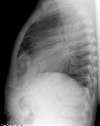

Morgagni Hernia:

The infant in the images below was referred for the evaluation of a "cystic anterior mediastinal mass." The "mass" was confirmed to be large bowel loops on a barium enema exam.

BE: